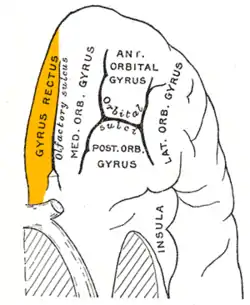

Orbital surface of left frontal lobe. Straight gyrus is shown in orange. | |

The portion of the inferior frontal lobe immediately adjacent to the longitudinal fissure (and medial to the medial orbital gyrus and olfactory tract) is named the straight gyrus,(or gyrus rectus) and is continuous with the superior frontal gyrus on the medial surface.